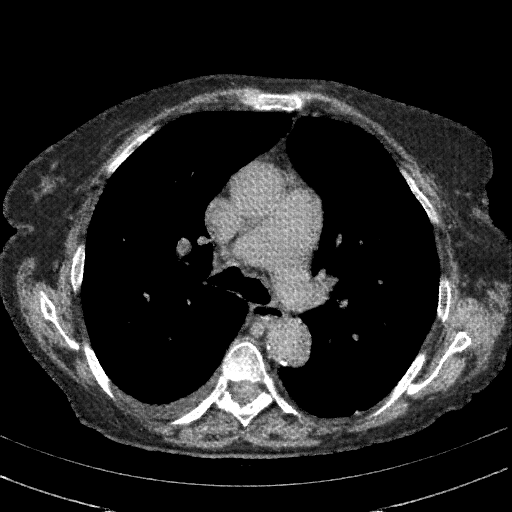

Targeted Slice 70 - Mediastinum Window Analysis (Generated vs Real Venous)

0.625

Mediastinum SSIM

56.4

Mediastinum RMSE

25.0

Mediastinum MAE

Average Mediastinum Window Metrics Across All Slices (153 slices) - Generated vs Real Venous

0.556

Mediastinum SSIM (Avg)

58.5

Mediastinum RMSE (Avg)

29.2

Mediastinum MAE (Avg)

Generated VENOUS CT scan (A→B translation)

Mediastinum window (WL 40, WW 400 β†’ Low βˆ’160, High +240)